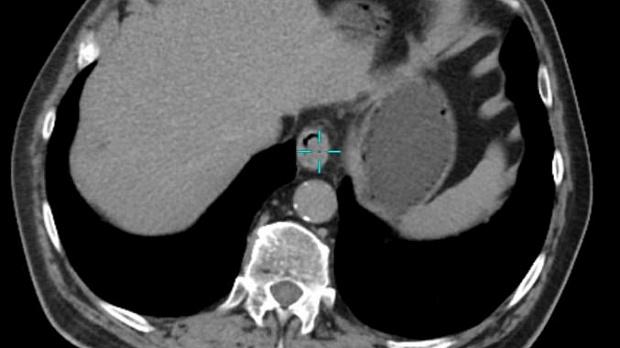

Иллюстрация №4: Рис. 4. КТ ОБП с внутривенным контрастированием. Гиперваскулярное образование пищеводно-желудочного перехода размерами 23 х 11 мм.

КТ ОГК и БП с контрастным усилением указывала на наличие гиперваскулярного образования по левому контуру области кардиоэзофагеального перехода, размерами 23 х 11 мм, с наличием кратерообразного углубления на поверхности, без признаков инфильтрации окружающей клетчатки (рис 4). Нижние параэзофагеальные лимфоузлы (ЛУ) размером до 7 х 5 мм, кардиальные ЛУ, ЛУ по малой и большой кривизне, пилорические и по ходу левой желудочной артерии размером до 2-4 мм, в области чревного ствола и общей печеночной артерии единичные ЛУ размером до 6 х 11 мм.